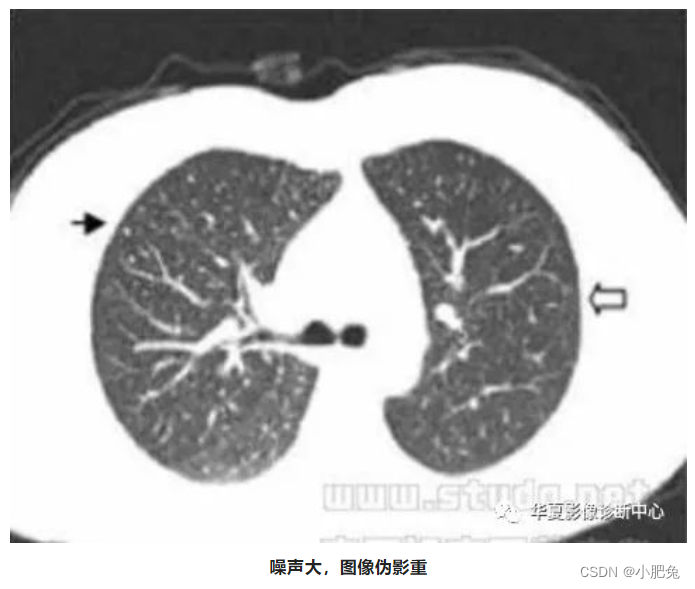

八、噪声引起的伪影

噪声的主要原因是入射射线光子数量不足。 如果扫描参数选择不当,或患者在扫描架内的位置偏移(偏离扫描野中心),可使入射射线光子数量不足,进而产生图像伪影(图像模糊)。

处理方法

正常情况下, 光子数越多信号越强、噪声越小, 反之则信号越弱、噪声越大。噪声所引起的伪影, 通常只要增加扫描条件即可避免。其他也可采用专用滤过算法, 也可使噪户伪影减弱。